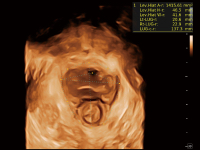

豐富的血流動(dòng)力學(xué)檢測(cè)技術(shù),可在不同醫(yī)療場(chǎng)景中高效捕捉血流信號(hào),助力臨床診療。

在傳統(tǒng)血流的基礎(chǔ)上優(yōu)化掃查和算法策略,能夠更好的抑制組織信息,提煉紅細(xì)胞運(yùn)動(dòng)信息,得到更高幀頻,高靈敏度和分辨率的血流信號(hào),還原更真實(shí)的血流動(dòng)力學(xué)。

通過(guò)光照模型,使二維血流顯示出立體的效果,增加血流的敏感性、成束性,減少外溢。可以和其他不同的血流技術(shù)聯(lián)合使用,融合不同技術(shù)的優(yōu)勢(shì)。輕松應(yīng)對(duì)微小血管,增強(qiáng)血流的立體效果,提升視覺(jué)敏感性。

通過(guò)創(chuàng)新的Matrix E自適應(yīng)濾波算法,能有效濾除軟組織和噪聲信號(hào),最大限度保留超低速微細(xì)血流的信號(hào);結(jié)合超長(zhǎng)時(shí)間域算法,極大提升細(xì)微血流的敏感性和空間分辨率,更真實(shí)的反應(yīng)組織、包塊的血流灌注情況。